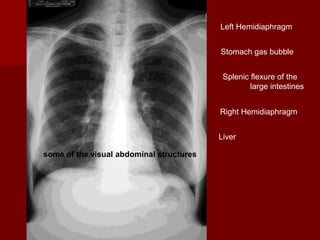

Left Hemidiaphragm

Stomach gas bubble

Splenic flexure of the

large intestines

Right Hemidiaphragm

Liver

some of the visual abdominal structures